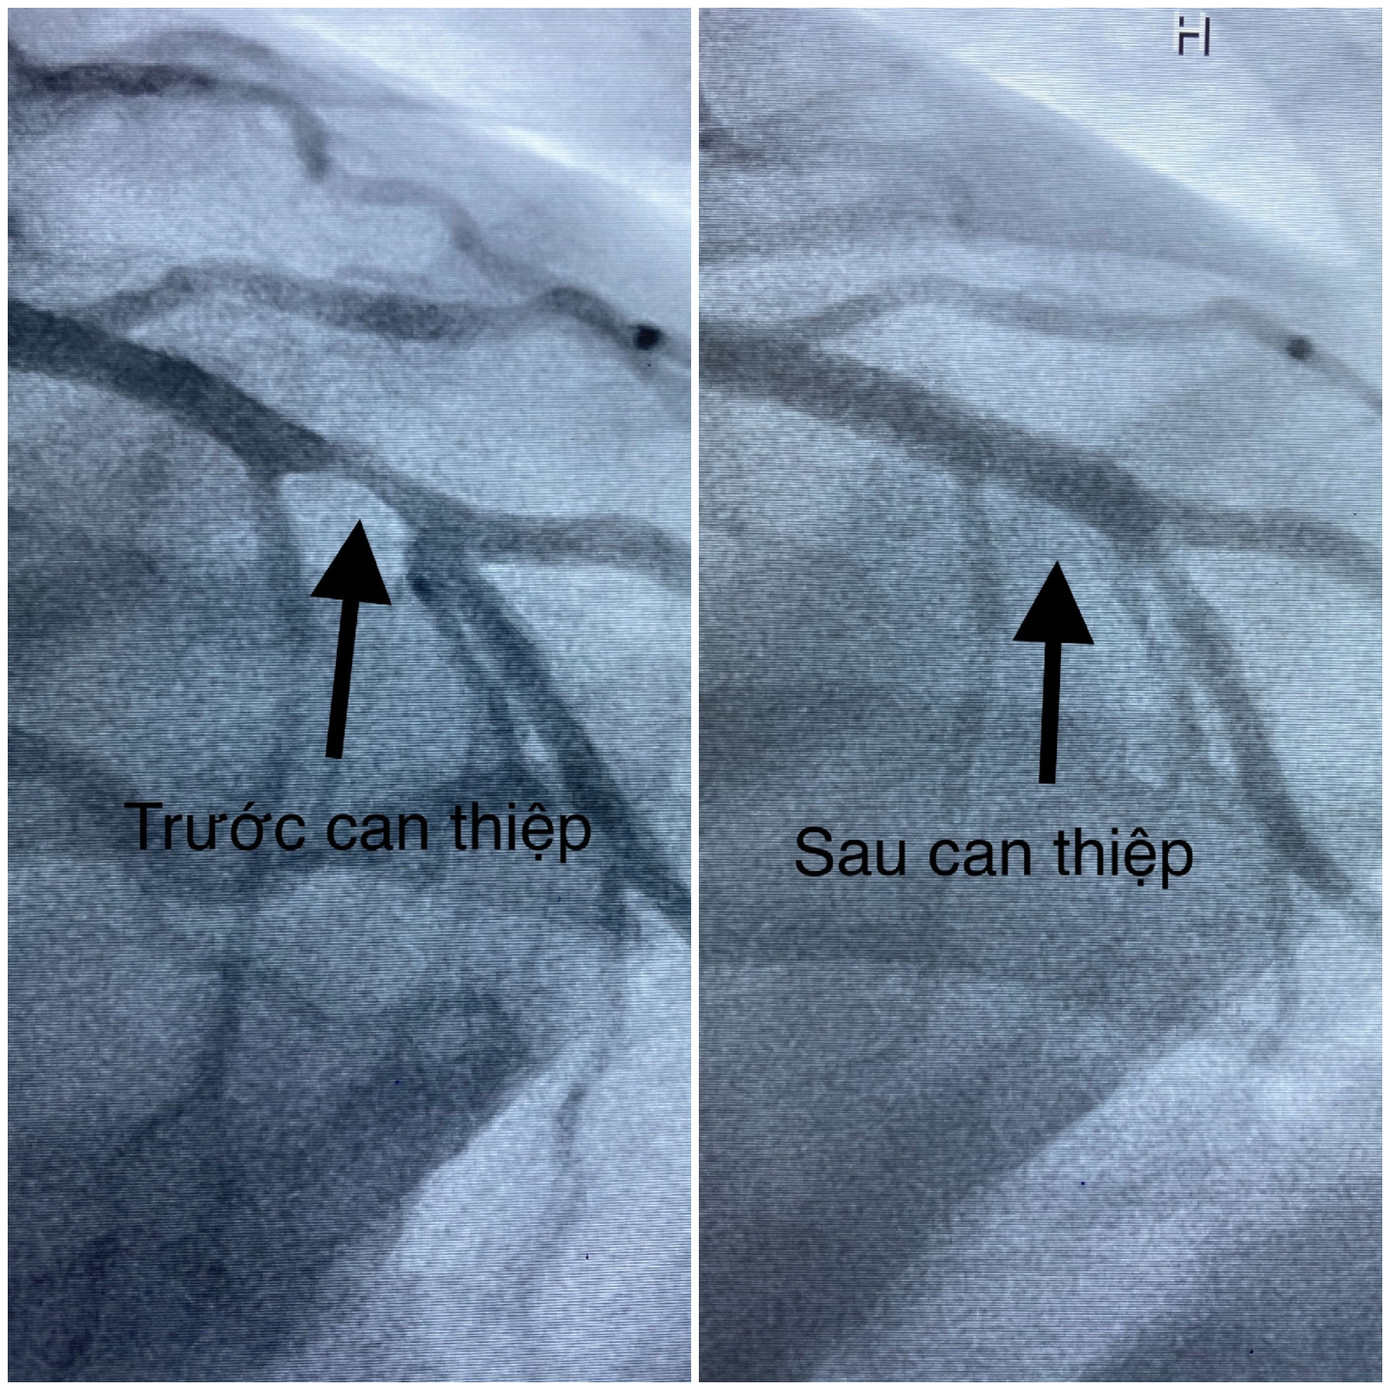

Hình ảnh động mạch vành trước và sau khi can thiệp. Ngay khi tiếp nhận thông tin, Bệnh viện Đa khoa Trung ương Cần Thơ tiến hành báo động đỏ nội viện và chuẩn bị sẵn sàng các trang thiết bị, phương tiện cấp cứu, thuốc và đặc biệt huy động các trưởng khoa và cả Ban Giám đốc bệnh viện cùng tham gia cấp cứu cho bệnh nhân.

Trước tình trạng nguy kịch, với nguy cơ tử vong cao, bệnh nhân được chỉ định chụp và can thiệp mạch vành cấp cứu. Kết quả cho thấy, ông T. bị hẹp nhánh liên thất trước đoạn II 80%, san thương không ổn định và can thiệp thành công bằng Stent phủ thuốc trong vòng 20 phút. Dựa vào các xét nghiệm, bệnh nhân được lọc máu liên tục cấp cứu suy đa tạng và kết hợp sử dụng hệ thống thăm dò huyết động theo phương pháp PICCO.